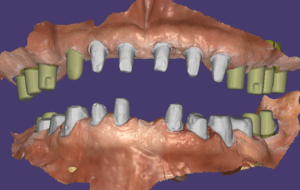

모든 임플란트는 골융합이 잘 되었고 스캔바디를 끼우고 스캔을 한 다음 디자인해서 치아를 만들었습니다. 저희 병원은 치기공 100% 모두 자체적으로 가공을 하고 있어요. 모든 장비를 다 갖추고 있구요. 기공을 제가 직접 하게 된 스토리는 길어서 다른 글에서 보시면 될 거 같아요. 아무래도 제가 임상에서 깨달은 부분을 디자인에 직접 적용하기 위함이 큽니다.

지대주 디자인이 된 모습이에요.

임플란트 보철 속에 이런 식으로 지대주가 들어있어요.